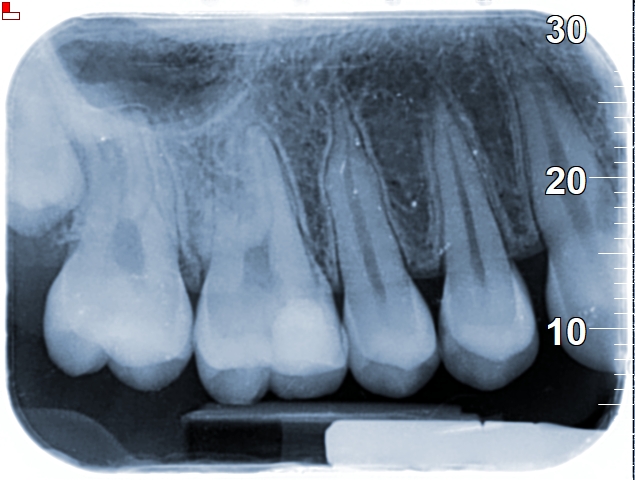

אותה מטופלת שן 26

אותה מטופלת שן 16

הסיפור של המטופלת לעיל מדגים באופן הטוב ביותר את החשיבות של גישה שמרנית יותר, המנסה להימנע מטיפול שורש. צילומי השיניים לעיל ניטלו לפני כשנתיים. בעת הגעתה למרפאתנו, הגיעה עם תלונה על כאבים בשן 26 (ראו צילום לעיל), לאחר שבוצע בשן זו טיפול שורש במרפאה קודמת בה היא הייתה. בשן בוצע טיפול שורש לפני כשנה טרם הגעתה למרפאתנו. הסיפור ארוך, אך בקצרה- בצילום סיטי (שבוצע בבית חולים מסיבות אחרות…) נראה כי טיפול השורש סבשן 26 היה נראה תקין לחלוטין (בד”כ יש 4 תעלות בשן זו בפה ומאוד נפוץ שמפוספת התעלה הרביעית אך אצל מטופלת זו היו רק 3 תעלות שורש שנאטמו יחסית טוב, לפחות רנטגנית). במהלך הבירור, המטופלת החלה לסבול מכאבים בשן 16, הוחלט לבצע VPT והיא נמצאת במעקב עד היום ללא כל תלונה על כאבים.